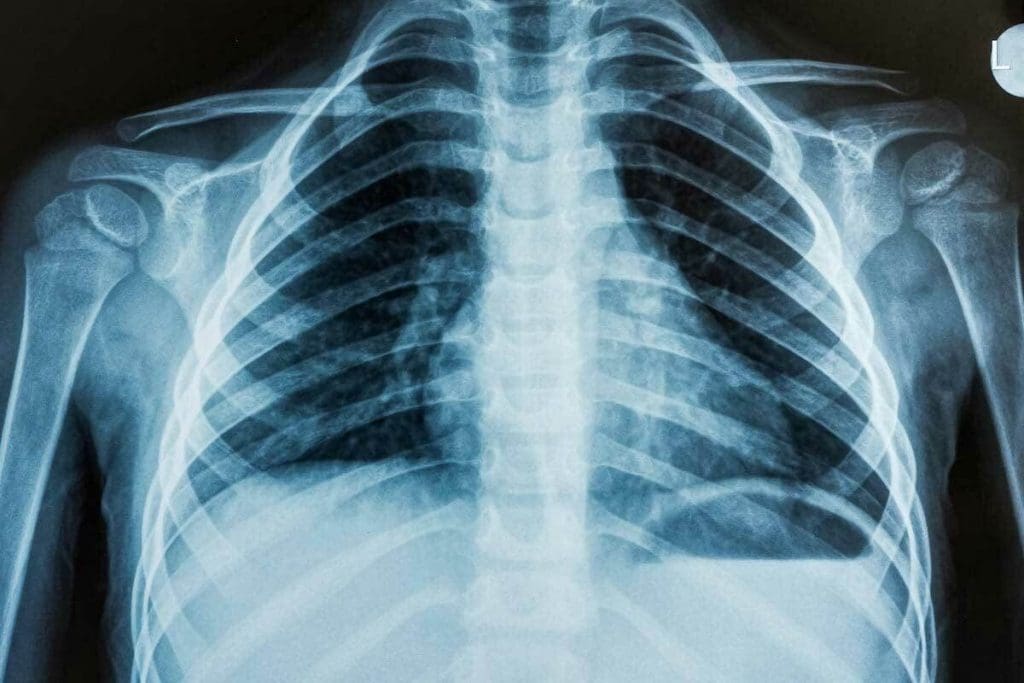

X-rays use electromagnetic waves to show us what’s inside the body. When an X-ray beam hits the body, different parts absorb it differently. For example, bones absorb more than soft tissues. This makes it possible to see detailed images of the body’s inside.

X-rays are used a lot for checking bones, lungs, and teeth. They are great for:

• Spotting bone problems like osteoporosis and fractures.

• Finding lung infections like pneumonia.

Understanding X-rays and their uses shows their importance in healthcare. They help us check bone health and lung conditions. X-rays are a basic but essential tool in medicine.